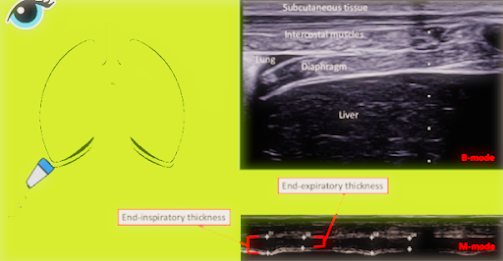

• Ultrasound Mode: B-mode (2D imaging) and optionally M-mode.

• Probe Placement and Imaging:

Preferred Site:

• Zone of Apposition: Where the diaphragm lies against the rib cage.

• Typically in the 8th to 10th intercostal space, mid-axillary to anterior axillary line (right side often clearer due to liver window).

1. Place the probe perpendicular to the chest wall, in a longitudinal orientation between ribs (intercostal)

2. Identify:

• Diaphragm as a three-layered structure:

• Hypoechoic (muscle) band between two hyperechoic lines (pleura and peritoneum).

• 3. Use B-mode to measure diaphragm thickness during:

• End-expiration (Tdi_exp)

• End-inspiration (Tdi_insp)

• 4. Optional: Switch to M-mode to visualize and measure thickness over time for better temporal accuracy.